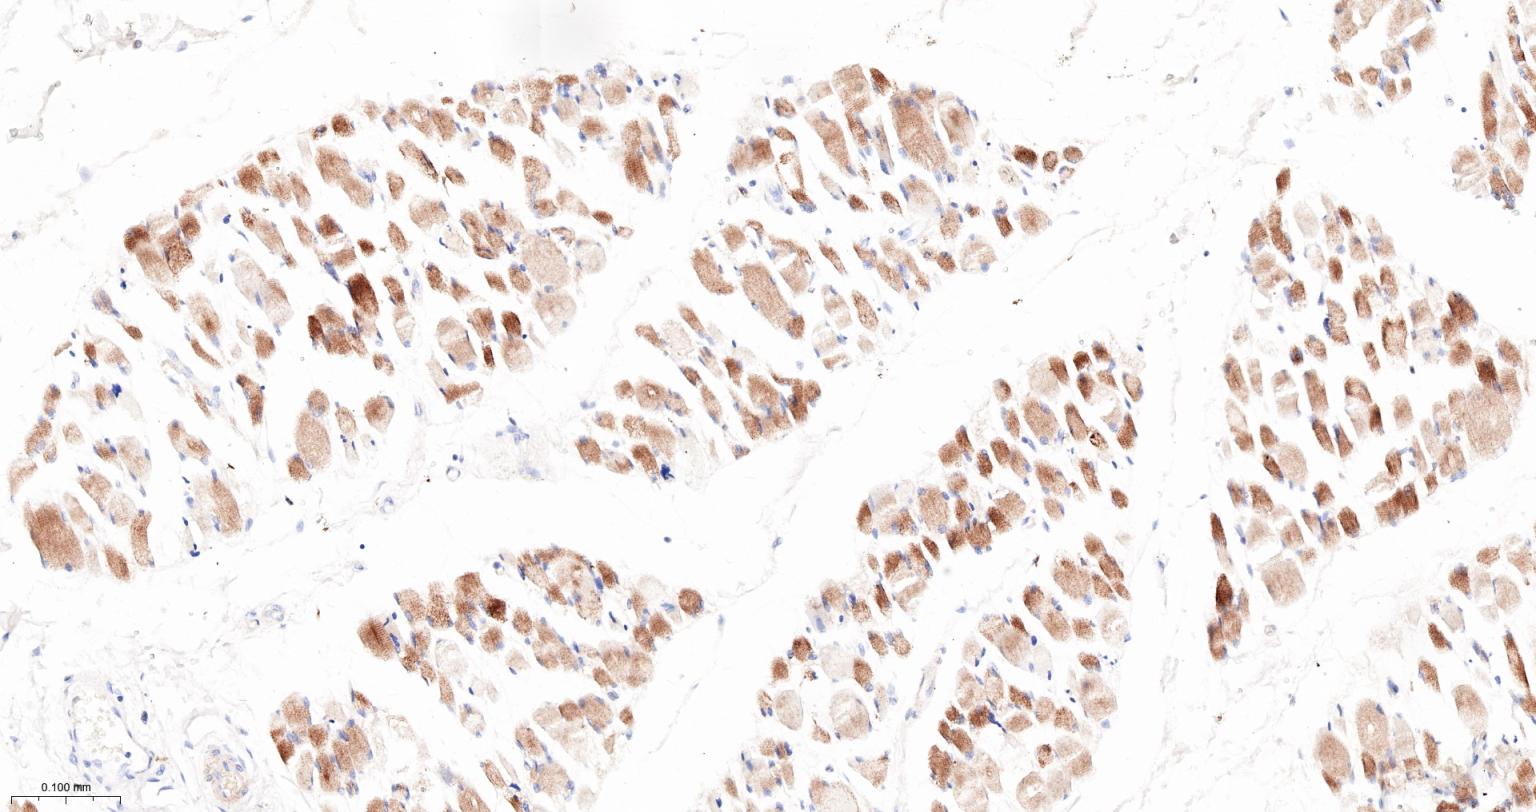

Paraformaldehyde-fixed, paraffin embedded Human Skeletal muscle; Antigen retrieval by boiling in sodium citrate buffer (pH6.0) for 15 min; The section was incubated with INPP4B Monoclonal Antibody, Unconjugated (bsm-61303R) at 1:200 overnight at 4°C, followed by conjugation to the bs-0295G-HRP and DAB (C-0010) staining.